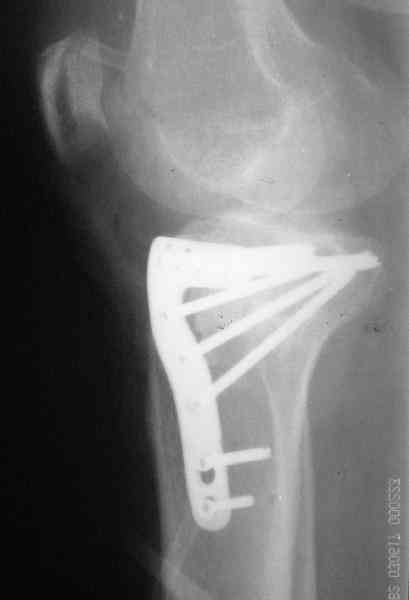

Abdurashid Turaev 24 Апрель 2008, 00:19

Уважаемые коллеги , друзья! всем большое спасибо! Очень интересные высококвалифицированные предложения, действительно этот форум для нас практических врачей как школа повышения квалификации и в конечном счете грамотное лечение больного Ч Е Л О В Е К А.

Наш план; доступ как подсказал Michael, по возможности репозиция, костная аутопластика дефекта метафиза, винты и спицы, АВФ и умеренная дистракция с шарнирными стержнями, и ранная пассивная разработка. Операцию планируем на следуюшей недели.